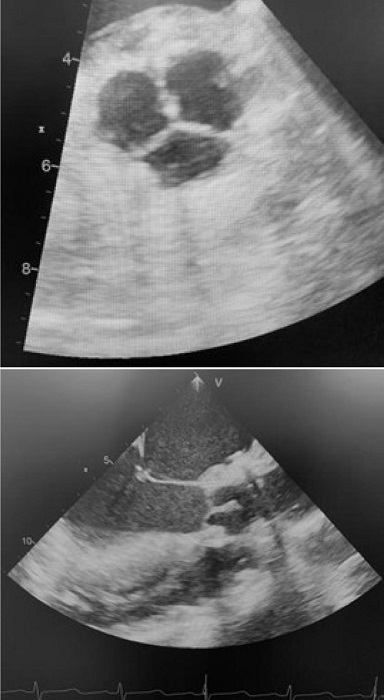

A transesophageal echocardiogram is performed after coming off CPB to assess valve morphology, valve area, coaptation surface of the cusps, absence of insufficiency, and transvalvular gradient (Figure 3).

Postoperative echocardiography showed good valve morphology, low transaortic gradient, and absence of aortic insufficiency in all cases except three patients. One showed moderate valvular insufficiency at the commissural level. Commissural closure was performed with a suture, and subsequent control showed absence of insufficiency. Two patients had severe central insufficiency due to poor cusp coaptation, and the valve was replaced with biological prostheses in both cases.

There were no cases of endocarditis or cerebrovascular accidents during follow-up. Transthoracic echocardiography was performed at 12 months of follow-up in 30 patients. Valve morphology was adequate, without calcifications or deterioration of the cusps. The mean gradient was 7.4 mmHg, and the peak gradient was 11 mmHg. One patient had moderate aortic insufficiency. It was decided to follow them clinically and echocardiographically before intervening. Two patients had severe insufficiency secondary to detachment of one of the neo-cusps at the commissural level (Figure 4). Valve replacement with prostheses was performed at two and four months post-surgery. Figure 5 shows freedom from aortic insufficiency > 3 and freedom from reintervention.